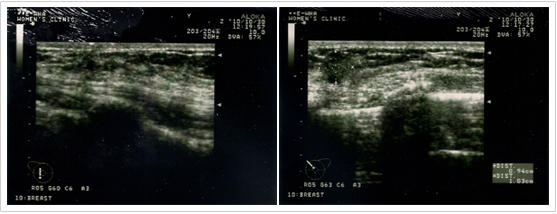

»ó±â ȯÀÚ´Â ¿ÞÂÊ °¡½¿¿¡ ¸ù¿ì¸®(BREAST MASS)°¡ ¸¸Á® Áø´Ù°í ³»¿øÇÏ¿© ÃÊÀ½ÆÄ °ËÁø°ú (ÃÊÀ½ÆÄ »çÁø)

Á¶Á÷ °Ë»ç ¸¦ ½ÃÇà ÇÏ¿© °Ë»ç °á°ú »ó±â Áø´Ü¸í(Á¡¾×¼º À¯¹æ¾Ï)À¸·Î Áø´Ü µÇ¾î (Á¶Á÷°Ë»ç°á°úÁö)